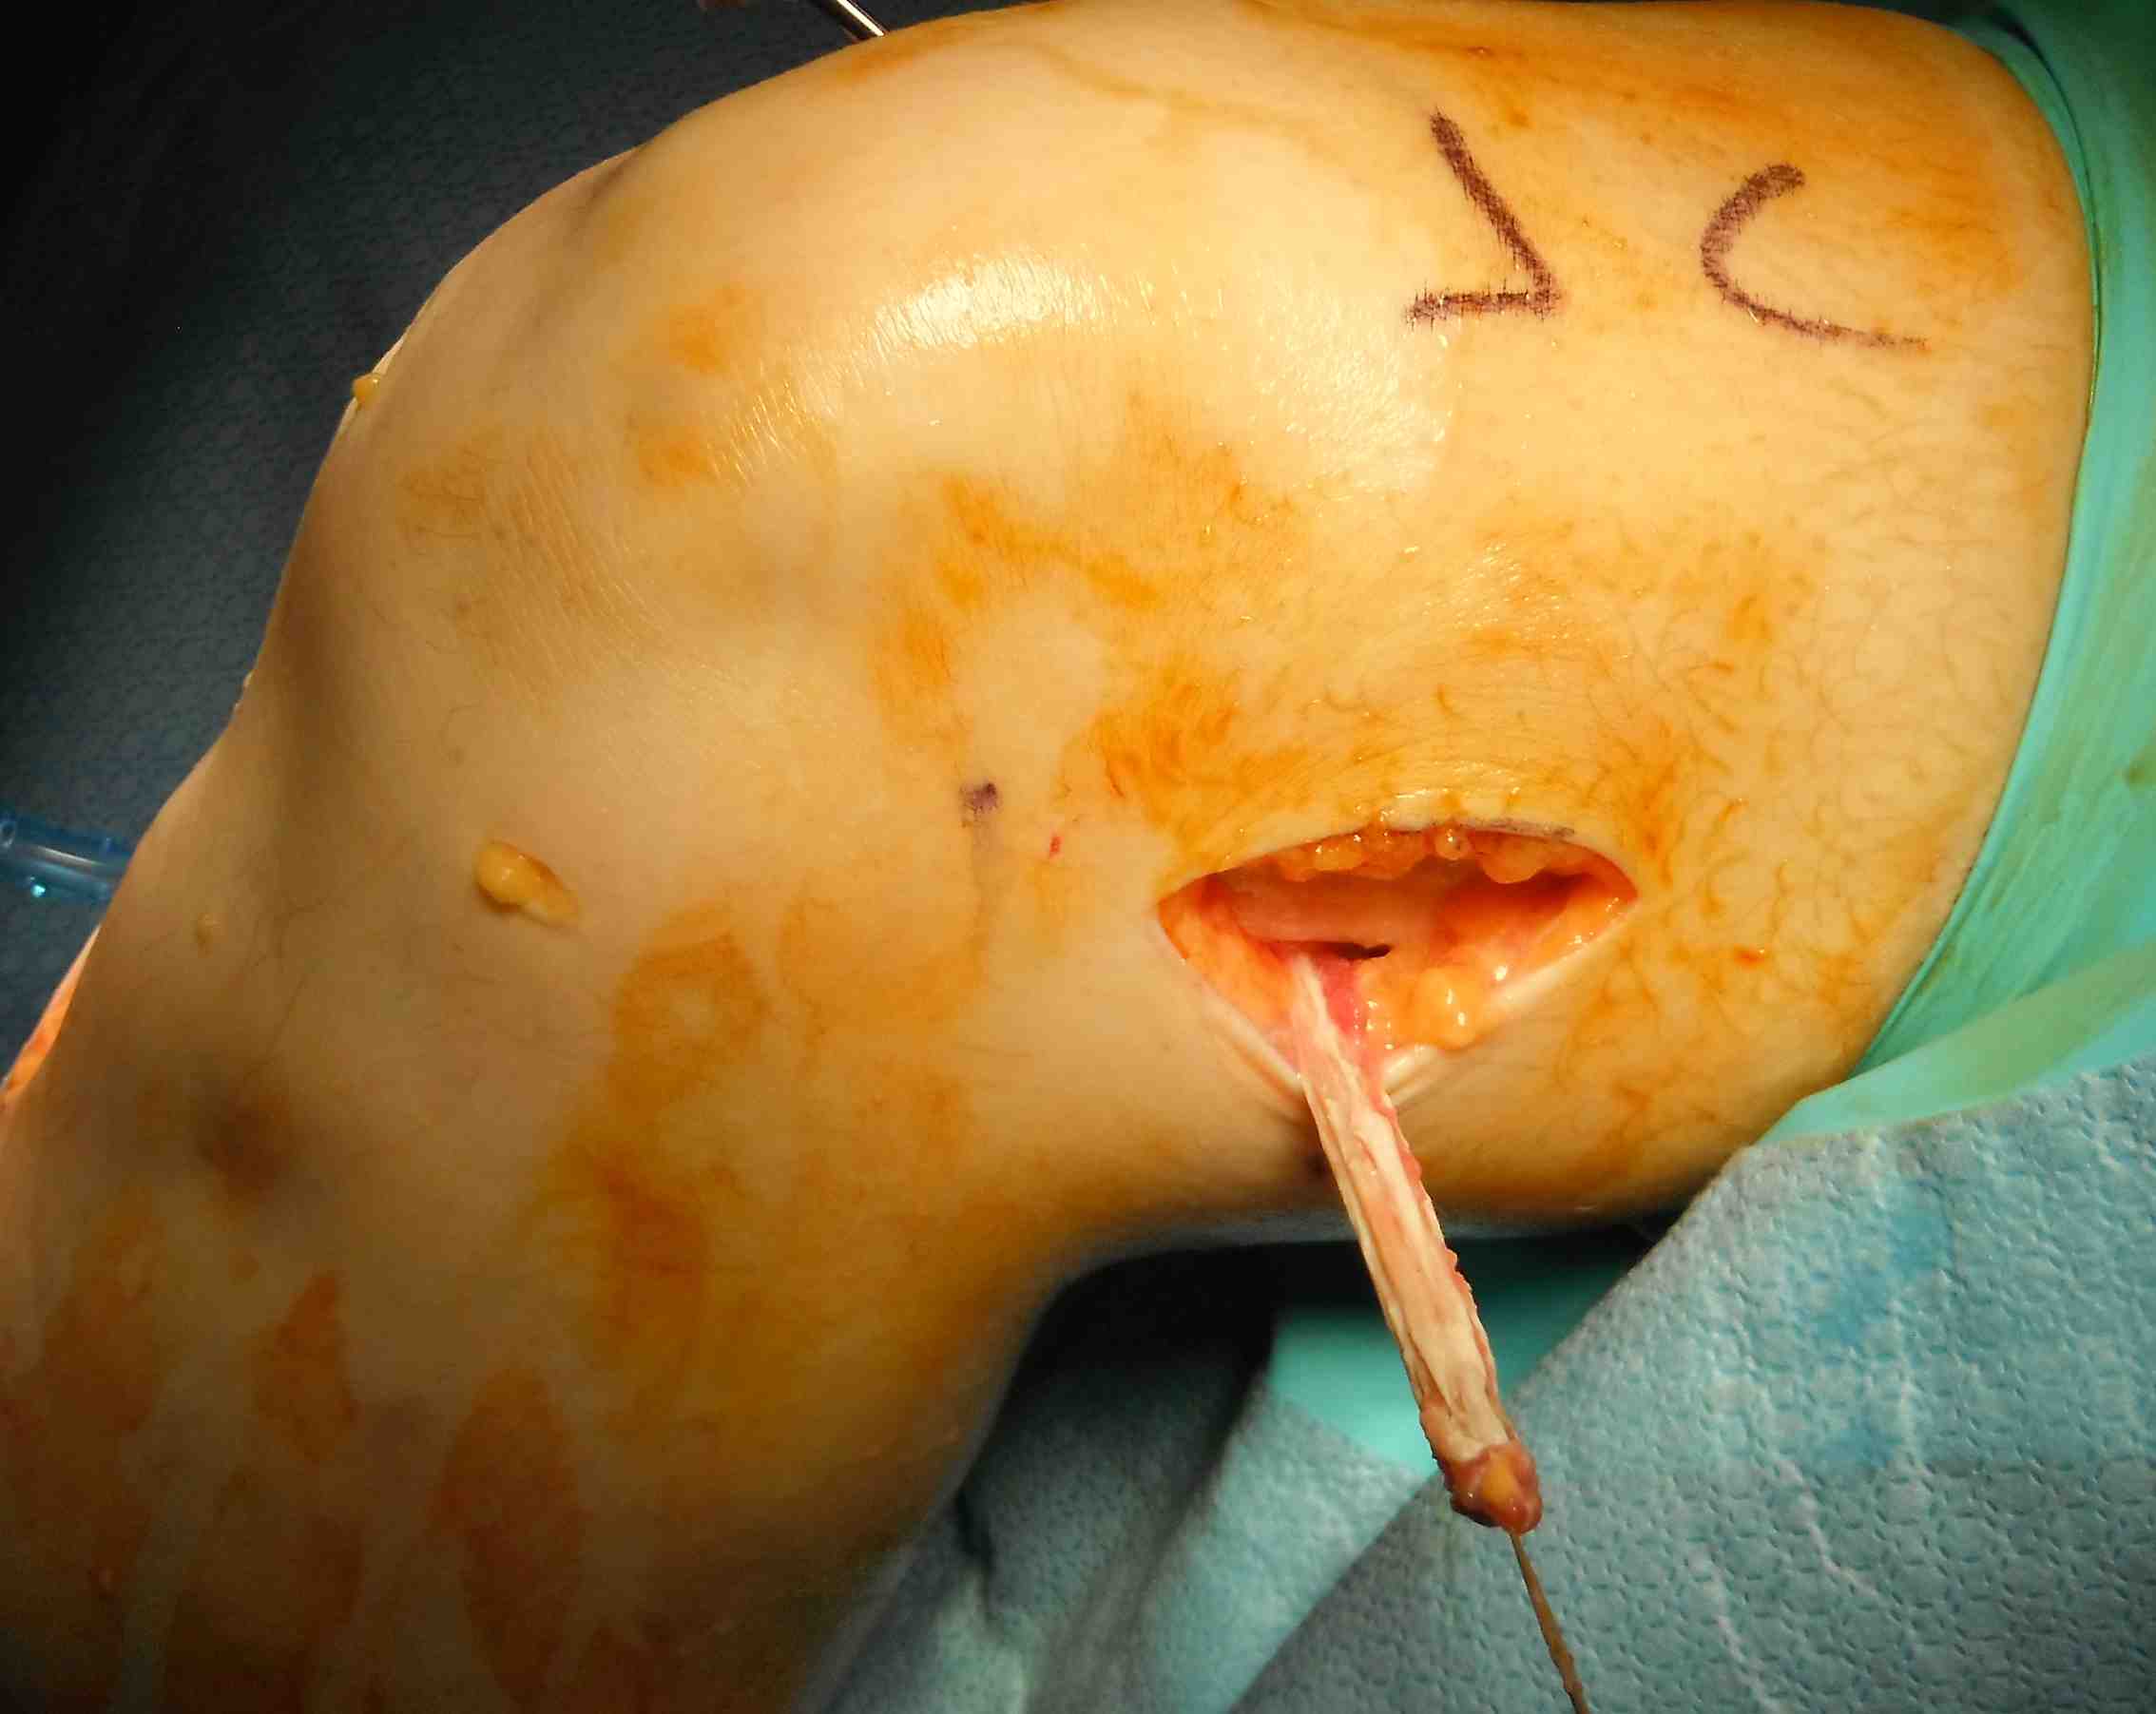

Pass curved hemostat

- from inside knee via medial arthrotomy

- pass around femoral condyle

- pass suture, retrieve graft